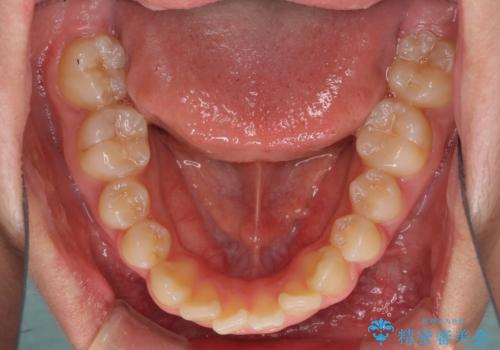

- 上下前歯のデコボコを改善したいとのことで来院された患者様です。

中学生と言うこともあり、1年強の短期間で終了しました。

歯磨きがしっかりとできないと虫歯になるリスクがありましたが、治療期間中は清潔な状態を保っていただけました。